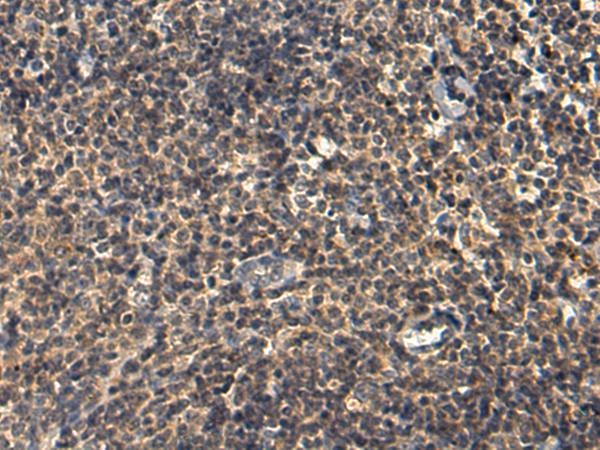

分类: 科研抗体货号: P08691别名: MST092; MST106; MST129; MSTP032; MSTP092; MSTP106; MSTP129应用: IHC反应种属: Human, Mouse, Rat